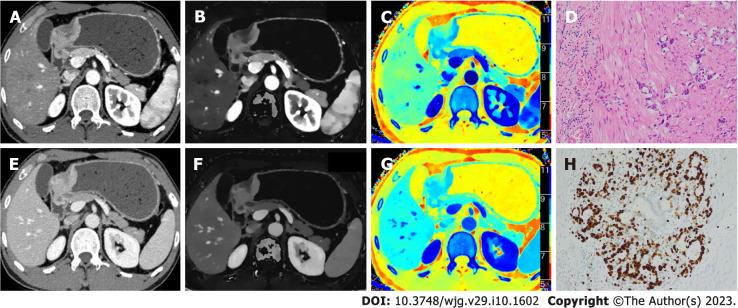

Dual-phase enhanced abdominal DLSDCT was performed preoperatively in 108 patients with gastric adenocarcinoma. Primary tumor monoenergetic CT attenuation value at 40-100 kilo electron volt (kev), the slope of the spectral curve (λ), iodine concentration (IC), normalized IC (nIC), effective atomic number (Z) and normalized Z (nZ) in the arterial phase (AP) and venous phase (VP) were retrospectively compared between patients with low and high Ki-67 expression in gastric adenocarcinoma. Spearman's correlation coefficient was used to analyze the association between the above parameters and Ki-67 expression status. Receiver operating characteristic (ROC) curve analysis was performed to compare the diagnostic efficacy of the statistically significant parameters between two groups.

Thirty-seven and 71 patients were classified as having low and high Ki-67 expression, respectively. CT, CT, CT, and Z-related parameters were significantly higher, but IC-related parameters were lower in the group with low Ki-67 expression status than the group with high Ki-67 expression status, and other analyzed parameters showed no statistical difference between the two groups. Spearman's correlation analysis showed that CT, CT, CT, Z, and nZ exhibited a negative correlation with Ki-67 status, whereas IC and nIC had positive correlation with Ki-67 status. The ROC analysis demonstrated that the multi-variable model of spectral parameters performed well in identifying the Ki-67 status [area under the curve (AUC) = 0.967; sensitivity 95.77%; specificity 91.89%)]. Nevertheless, the differentiating capabilities of single-variable model were moderate (AUC value 0.630 - 0.835). In addition, the nZ and nIC (AUC 0.835 and 0.805) showed better performance than CT, CT and CT (AUC 0.630, 0.631 and 0.662) in discriminating the Ki-67 status.